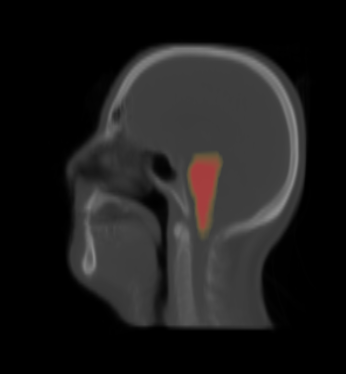

- We have 20 datasets for H&N including lungs and chests. For example

- We selected the ROI of every data excluding lung and chest. For each data there exist the segmentations of brain stem, left and right parotids. For example

- We constructed the average atlas of 20 datasets of ROI, and merged the segmentations into the average atlas. These segmentations are the probability maps of

brain stem, left and right parotids.